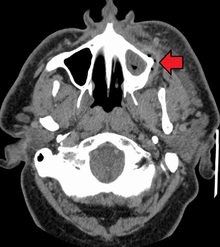

Dental caries can also cause bad breath and foul tastes.[14] In highly progressed cases, infection can spread from the tooth to the surrounding soft tissues. Complications such as cavernous sinus thrombosis and Ludwig angina can be life-threatening.[15][16][17]